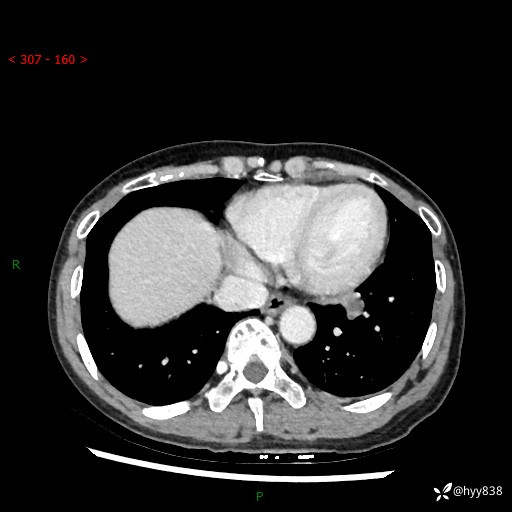

【检查】:胸部CT平扫+增强

各期CT值:40hu 57hu 49hu